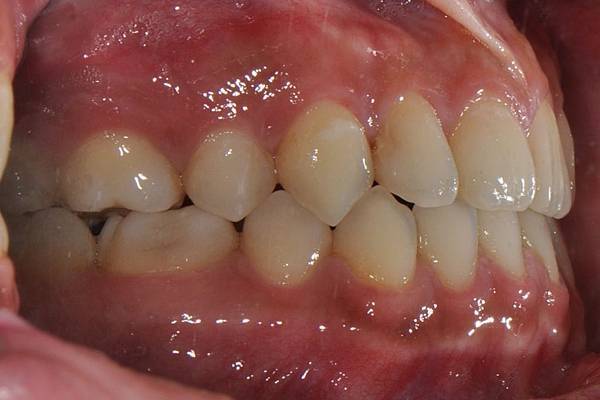

戽斗下唇突出改善案例

本案例因為考量到患者下唇突出

便建議拔除上下四顆小臼齒將

下唇內收

也改善了

前牙錯咬

的問題~

治療前/治療後

-以上案例由林昇進醫師提供